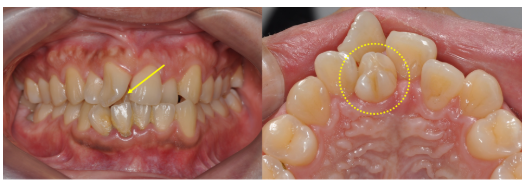

20대 남성 환자로, 입천장 쪽에 과잉치가 맹출되어 있었고 오른쪽 앞니가 180도 회전된 상태였습니다.

→ 과잉치를 발치하고 교정치료를 통해 앞니 배열을 정상화했습니다.